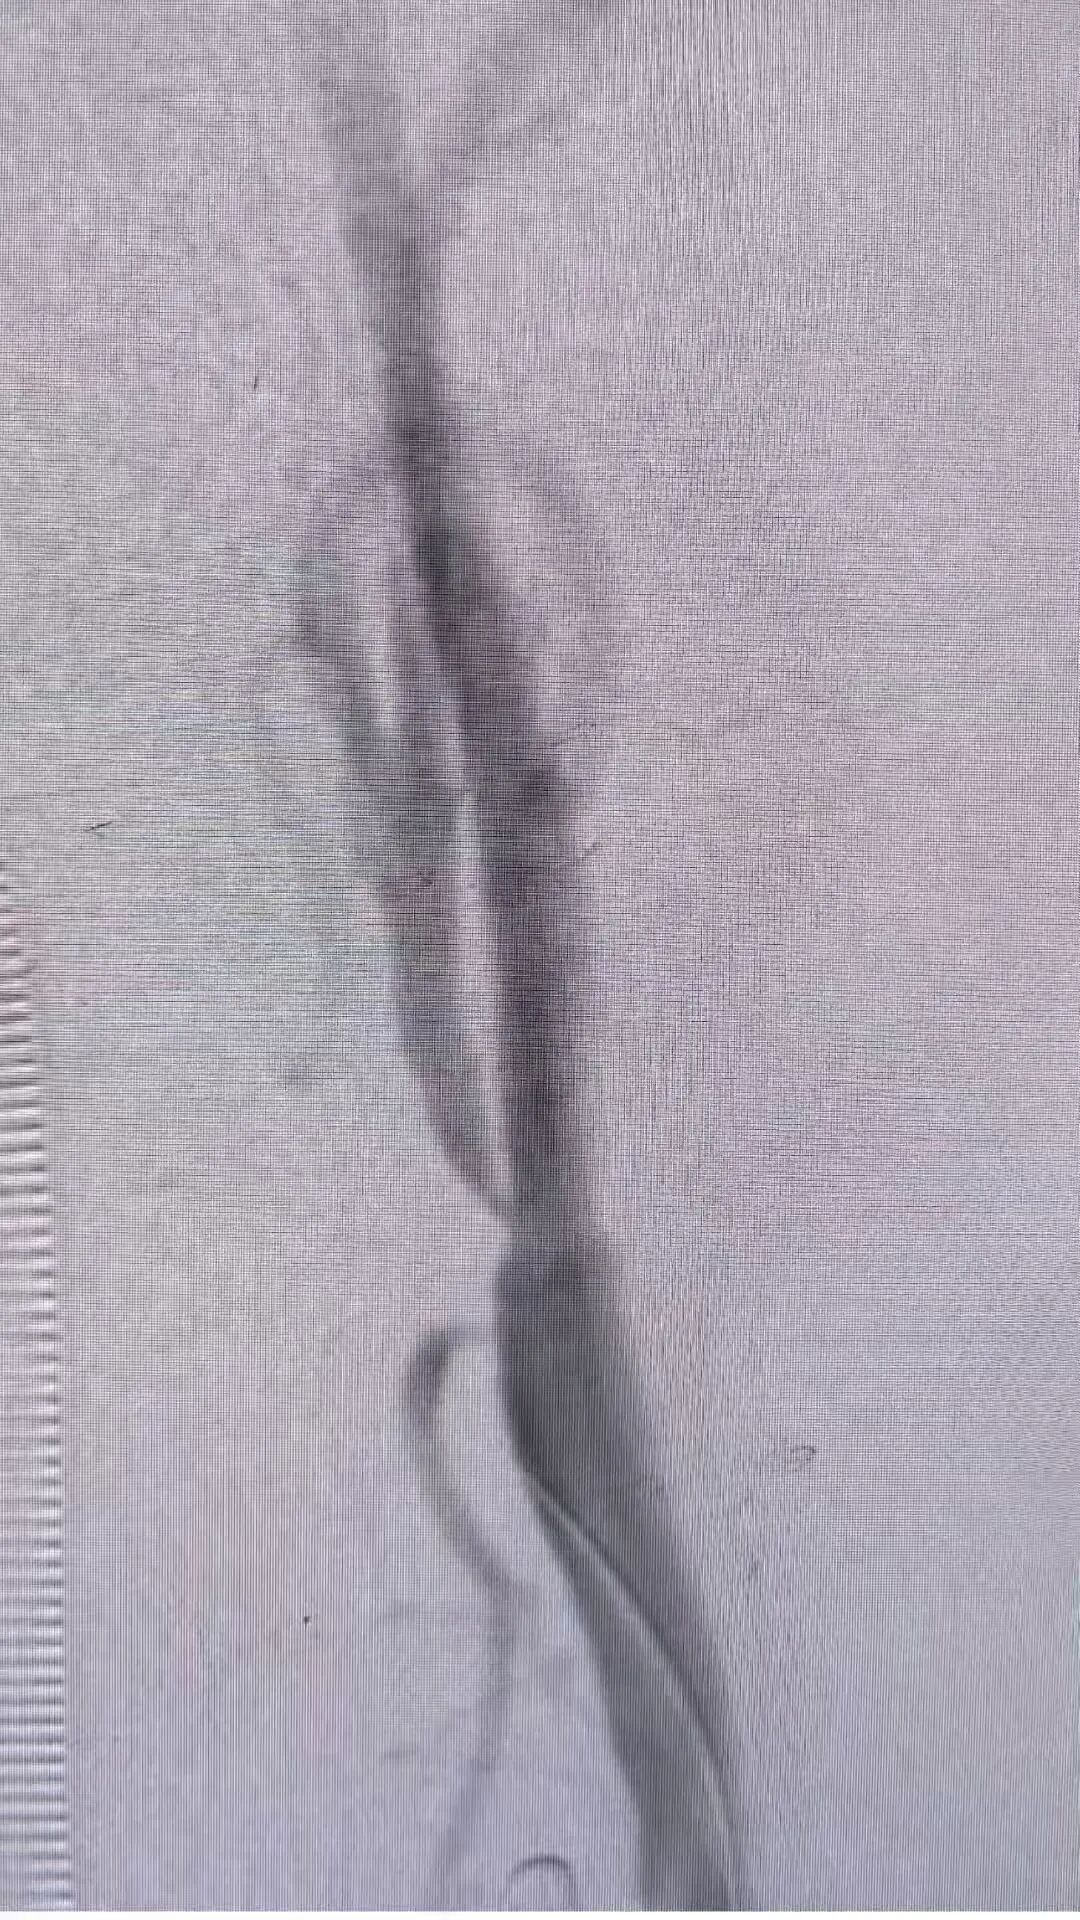

术前及术后造影图像: